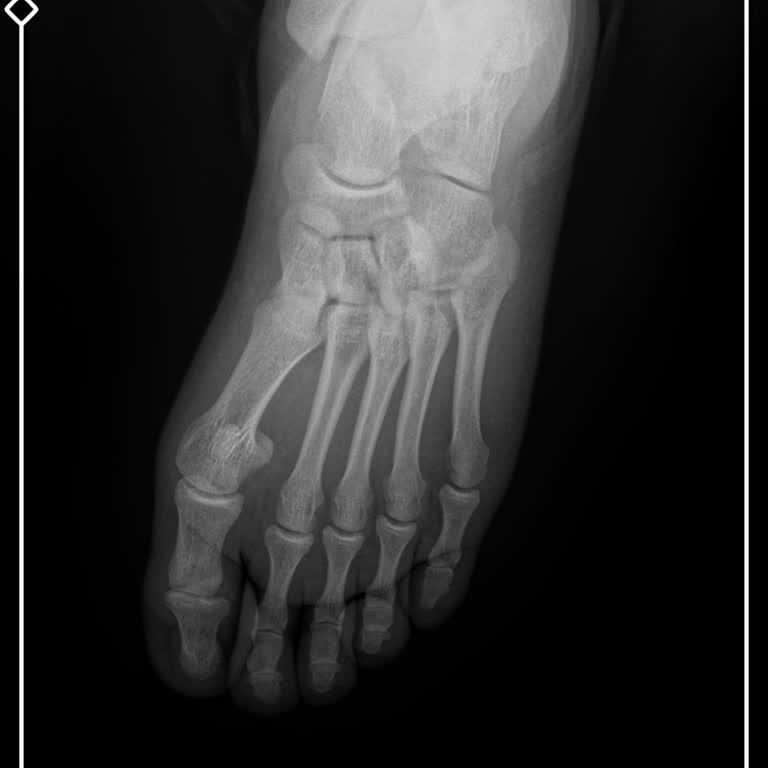

Acil Serviste Görmezden Gelinen Kırık Nedeniyle İşe Başlama Gecikmesi

10 Ocak sabahı saat 06.50 civarında Menderes Devlet Hastanesi acil servisine, ayağımda ciddi bir hasar olduğu için başvurdum. Sarı alanda ki bayan doktor röntgenimin çekilmesini istedi ve çekildi. Aynı bayan doktor bana herhangi bir problem olmadığı, sadece ilaç kullanmam gerektiği söylenerek acilde...